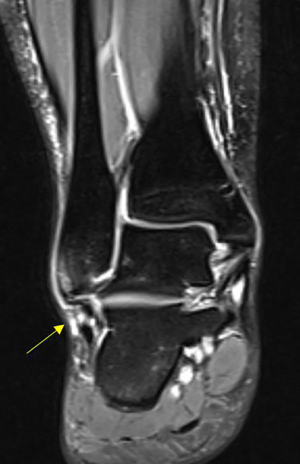

Synovitis was defined as synovial membrane thickening in T1-boosted sequences and increased signals in T2-boosted sequences (35). Representative MRI imagines are presented in Figures 1-10 in order to illustrate the definition of each condition.